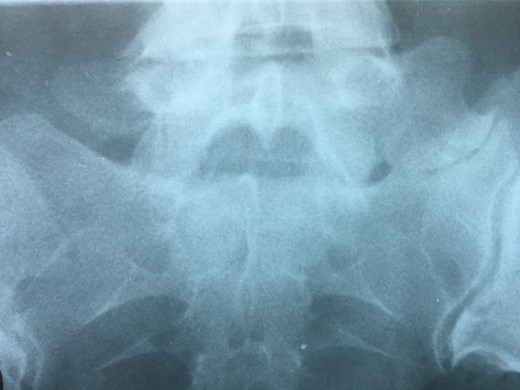

Showing the protective effect of the limitation of the motion in the distal disc to the anomaly.